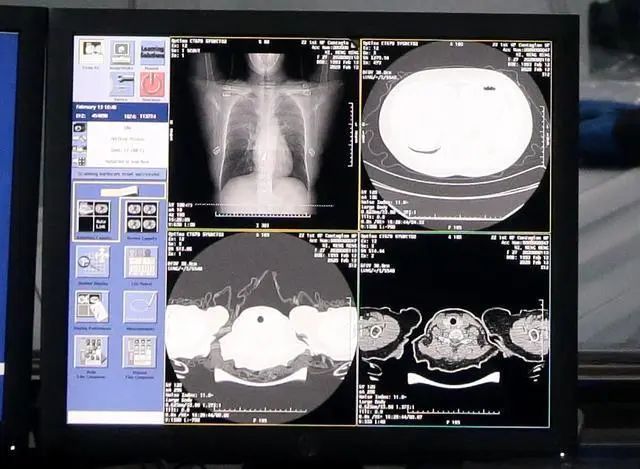

這些身懷絕技的機(jī)器人離不開它的核心技術(shù),就是人工智能AI。AI在此次疫情的醫(yī)療診斷和結(jié)果分析上也是大顯身手。武漢火神山醫(yī)院上線的達(dá)摩院AI,就大大提高救治效率,降低病死率,實(shí)現(xiàn)精準(zhǔn)診斷。

阿里巴巴集團(tuán)科技線公關(guān)林俊特:20秒就能給出96%準(zhǔn)確度的CT影像分析結(jié)果,可精準(zhǔn)識(shí)別病灶位置并算出病灶占比的變化數(shù)值,捕捉患者治療全程病情變化的蛛絲馬跡。AI診斷覆蓋新冠患者入院到出院全過程,幫助醫(yī)生及時(shí)調(diào)整診療方案,降低重癥轉(zhuǎn)化率。

達(dá)摩院AI的CT影像分析結(jié)果